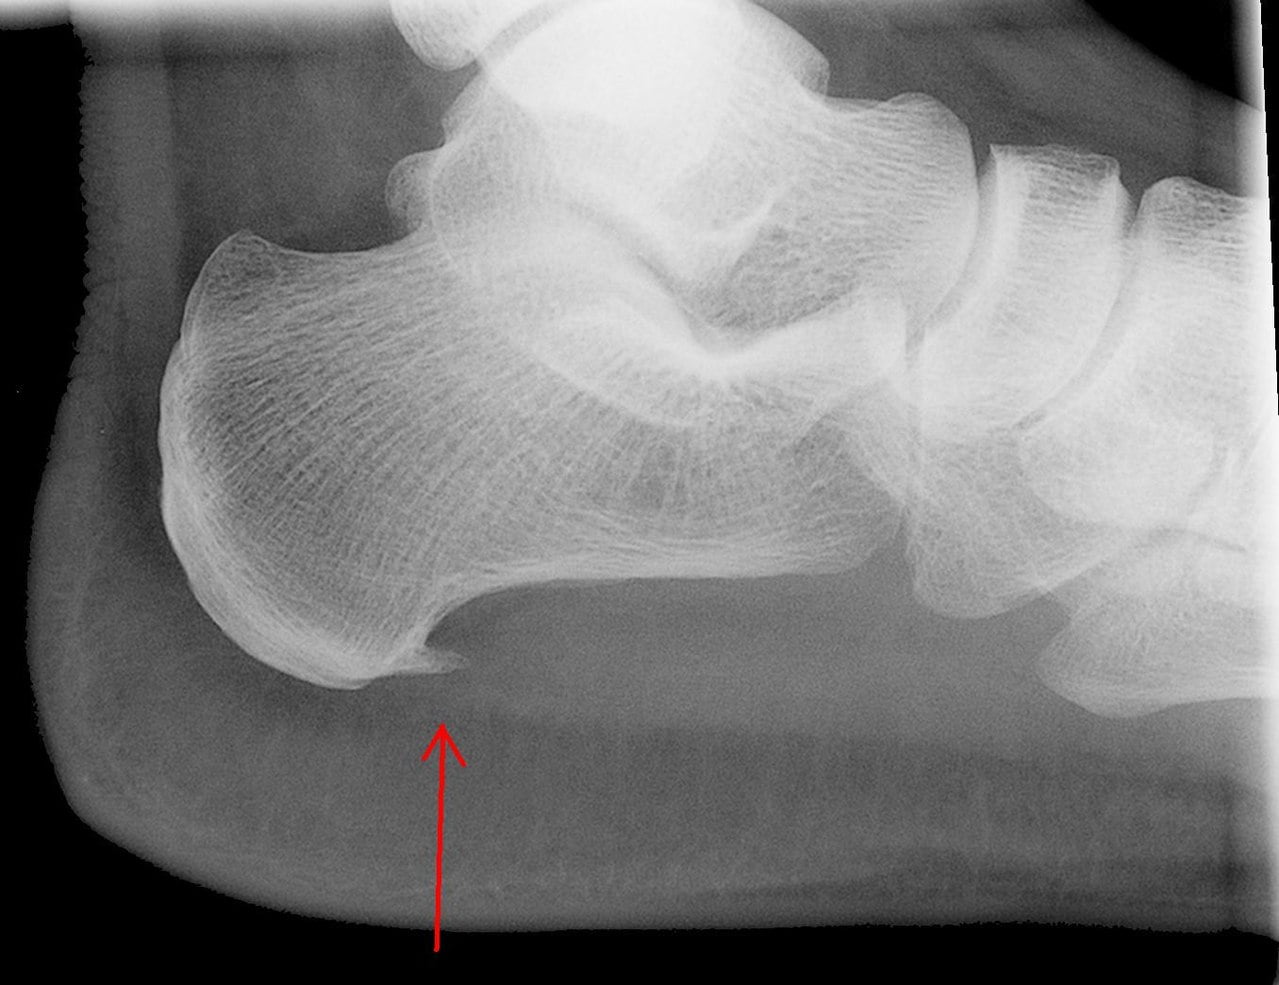

- Pintenul osos apare frecvent la baza calcaiului datorita suprasolicitarii neobisnuite care favorizeaza generarea unei proeminente noduroase la suprafata osului calcaneu. In momentul in care aceste proeminente apasa pe tesuturile din jur si pe nervi si duc la iritarea acestora provoaca disconfort si durere in timpul mersului. Degetele lungi si obiceiul de a purta frecvent pantofi cu toc inalt poate contribui la formarea osteofitelor.